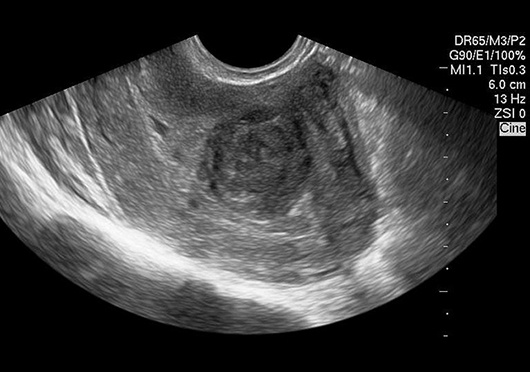

Как обнаружить миому?

1. УЗИ — самый простой и доступный метод

-2